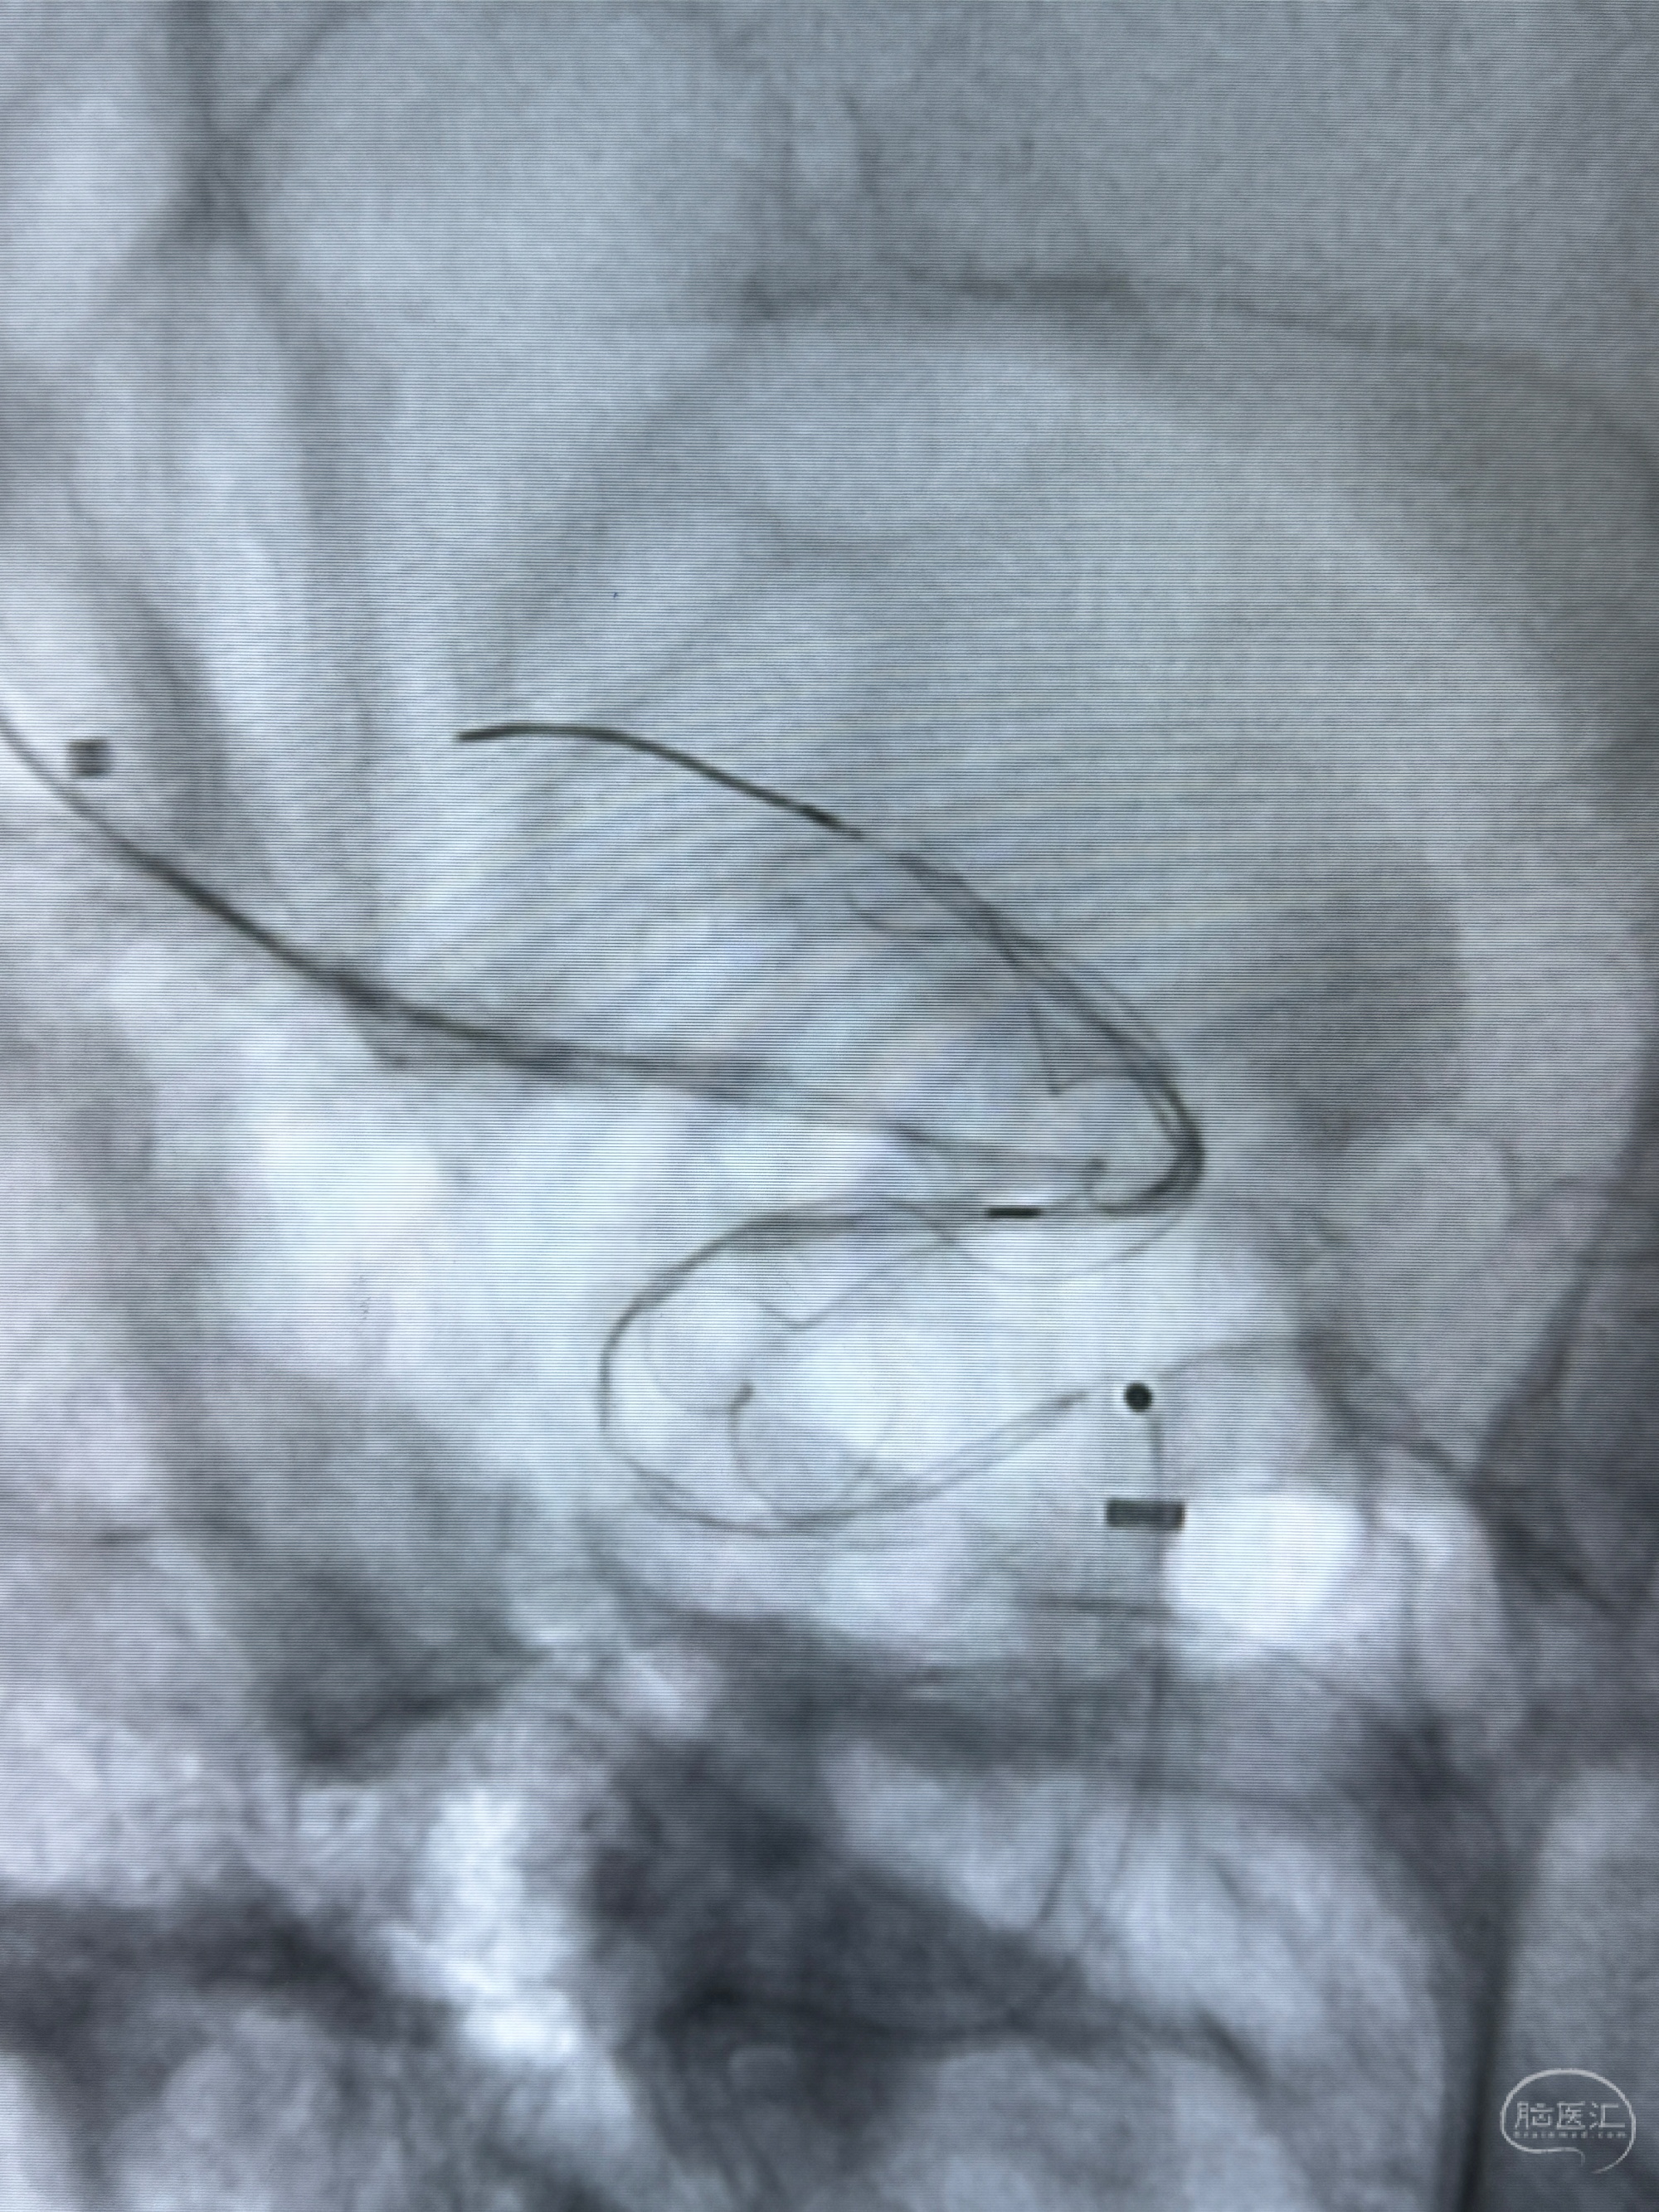

逐帧图像展示歪着脖子释放支架,旁边吩咐助手手机摄影、拍照留像(透视机不能留影像)

接下的视频为释放支架的过程及试图确认支架与血管的关系

看动脉瘤内造影剂滞留,未见明确射流,遂撤出预留的栓塞微导管,快速结束手术,经导引导管灌注替罗非班250ug。